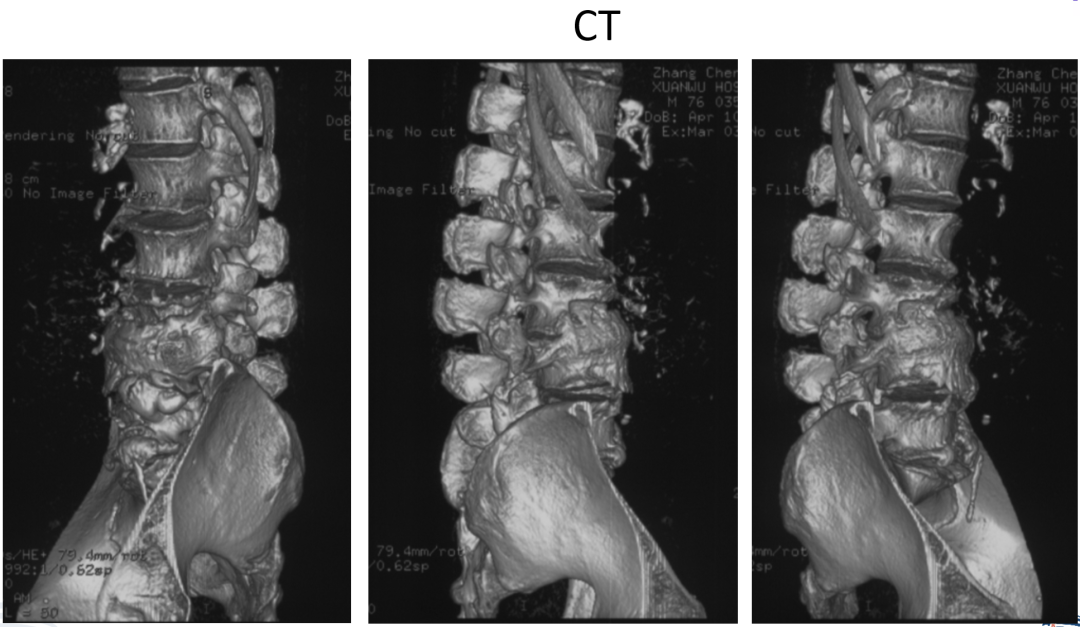

讨论主题:L4压缩骨折伴脊柱侧后凸畸形

影像资料:

腰椎侧后凸畸形

腰椎陈旧性压缩性骨折(L4)